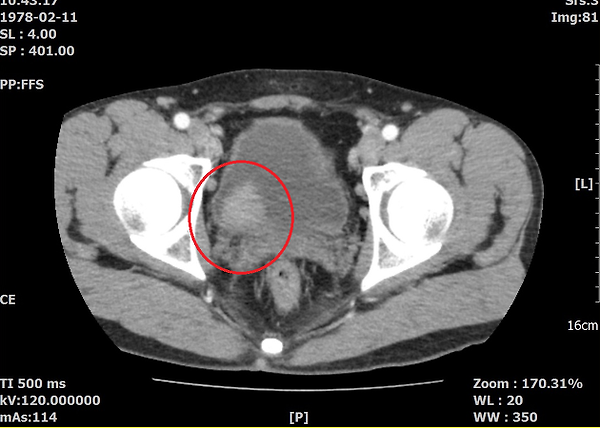

위사진은 암으로 추측되는부분이라도 개인병원 의사가 찾아주신 자료 중 하나입니다.

이게 맞을까요? 첫번째  2011년, 그다음 2015년 세번째도 2011년 그다음 2016년입니다. ....

아. 정확히 보이시네요.

첫번째 사진 2011년 4월22일 ENHANCE CT 영상에서도

동그라미 쳐진 부분(화살표) 부분이 조영증강된 것이 확인이 됩니다.

나머지도 보시기 쉽게 동그라미 표시를 해드렸습니다.